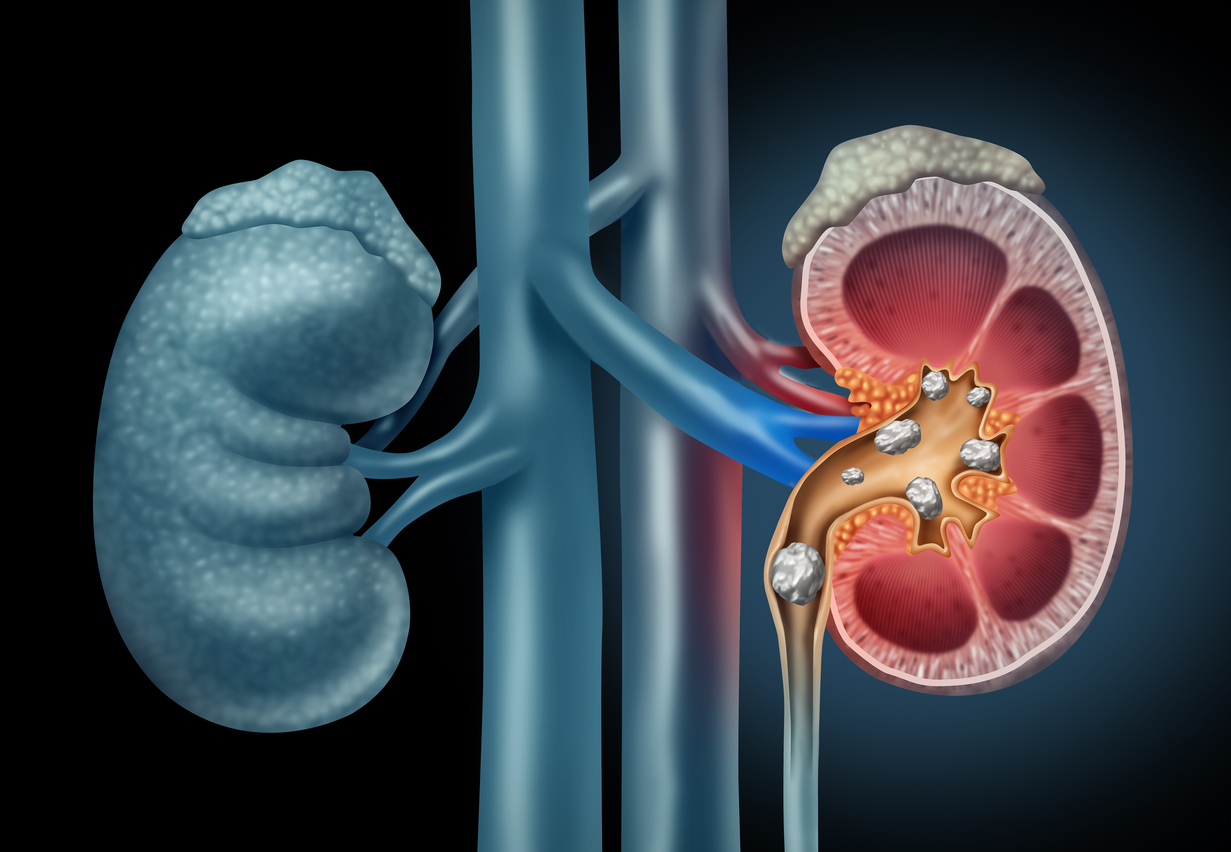

Πέτρες στους νεφρούς: Πρόκειται για μικρές και σκληρές αποθέσεις. Αυτές σχηματίζονται στους νεφρούς, με τη μείωση των ούρων. Μπορεί να σχηματιστούν και με την αύξηση κάποιων ουσιών. Όμως, ορισμένες τροφές βοηθούν στην αποτροπή του σχηματισμού των λίθων. Από εκεί και πέρα, μια πέτρα στο νεφρό είναι ένας σχηματισμός από μέταλλα. Αυτός μπορεί να έχει προκληθεί από μια σειρά διαφόρων αιτιών.

Πέτρες στους νεφρούς – Συμβουλές για την υγεία: Κοινά είδη

– Πέτρες οξαλικού ασβεστίου

– Πέτρες φωσφορικού ασβεστίου

– Στρώσεις από ρητίνη

– Πέτρες ουρικού οξέος

– Πέτρες από κυστίνη